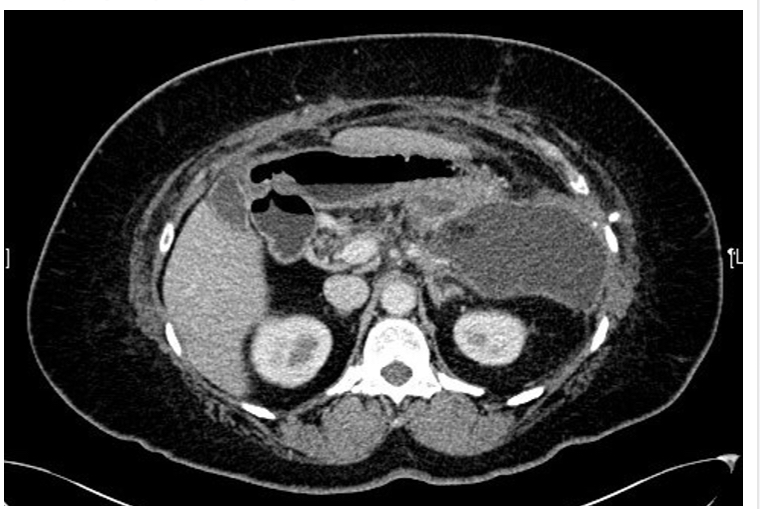

drainage could entail

*diagram shows percutanoues CT drainage*